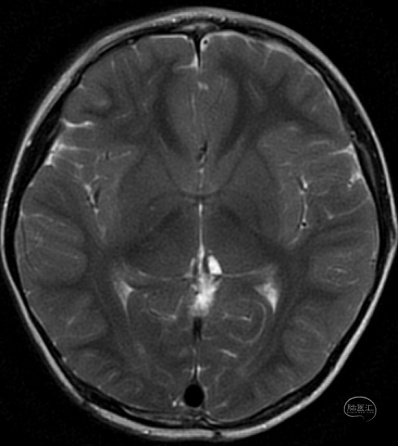

3岁男性患儿,间断头痛两个月入院,头部MR检查结果提示松果体区占位病变并梗阻性脑积水。

头部MR检查T2水平位显示松果体区囊实性占位病变,同时表现侧脑室及三脑室轻度扩张。

矢状位MR可见松果体区占位病变。